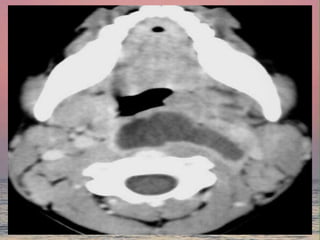

Cavernous sinus thrombosis

Clinical features

• Marked edema and congestion

of the eyelids and conjunctiva

• Proptosis and ptosis

• Ophthalmoplegia and dilated

pupil

• Papilloedema

• Fever

• Deprressed level of

consciousness

Treatment

• AB

• Heparin

• Treatment of odontogenic causes